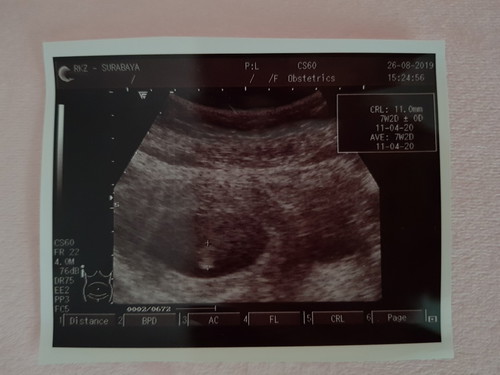

USG sdh terditeksi janin & DJJ legaaa sekalii

Haiii bundaa smua mau membagi kebahagiaan hehe.. lega banget hari ini usg untk lihat prkembangan janin dan DJJ nya.. trnyata sdh brkembang dan sudah ada DJJ nya .. 2mnggu yg lalu msh berupa kantong.. dan skrg uda ad isinyaa... lgsg seneng luar biasa ?? gak sabar untk menunggu prkembangan slnjutnya walaupun mual muntah ttp brlanjut ?? tetap smngaaattt ??